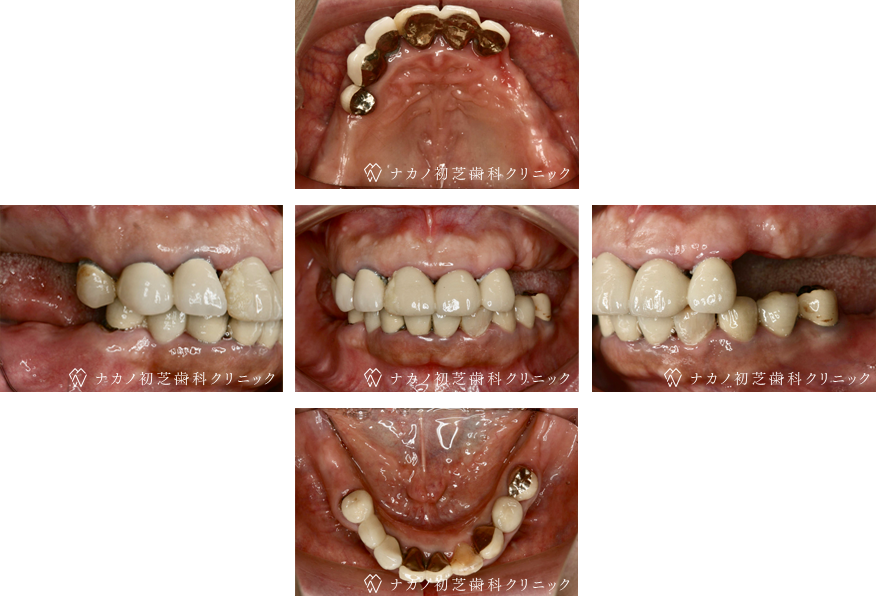

インプラント・7本 (70代男性)

-

BEFORE

AFTER

年齢 70代男性

治療内容 インプラント治療7本(骨造成の併用)

インプラント治療とは、歯を抜いた所にチタン製の人工歯根を埋入し、その上に歯を入れる方法です。骨を増やすことで、より審美的に治療が出来ました。費用 1本 400,000円(税込 440,000円)

リスク・副作用

腫れ・疼痛・違和感を感じるなどの症状を生じることがあります。